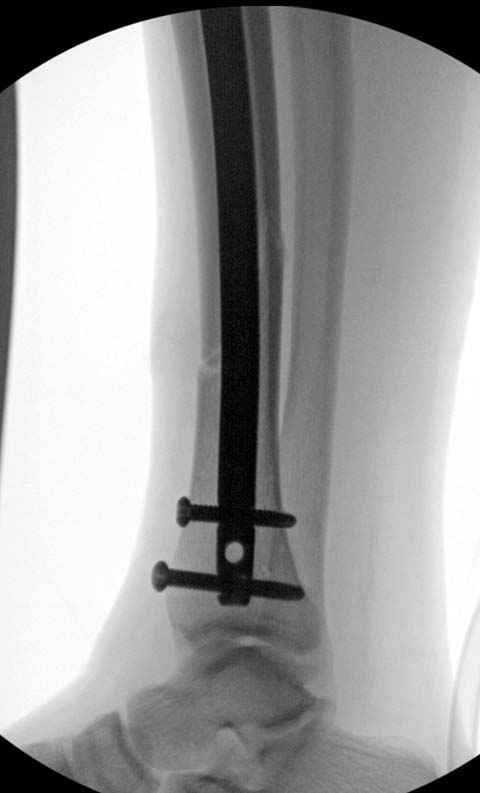

Разбор любого случая кому-то поможет лучше ориентироваться в решении вопросов, потому что в нашей работе встречаются разные связанные и несвязанные с мастерством хирурга ситуации. Возможно, отсутствие полного набора гвоздей повлияло на выбор короткого имплантата, имеется угловая и ротационная деформации. Независимо от локализации, стабильность создается, когда гвоздь проксимально не глубже 1.5 см (облегчает удаление) и дистально доходит до epiphyseal scar.

Здесь несколько снимков изолированного перелома большеберцовой с интактной малоберцовой. Weber clamp, блокирующие спицы и риминг в центре канала отрепонировал перелом....

В нашем распоряжении были все размеры гвоздей, но взяли этот.

Следующий размер на 15 мм больше и доходил до уровня сустава. Иногда даже самая идеальная фиксация не гарантирует сращение, надо оставить запас для динамизации. Дистально исчерпан лимит, а проксимально достаточно места...